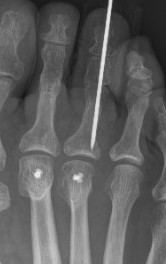

+/- screw fixion

+/- plantar plate fixation

- 278 Weil osteotomy

- 195 fixed with screw - revision rate 25% (primarily MTPJ arthrolysis)

- 83 without screw - revision rate 10%

- no difference in clinical outcome